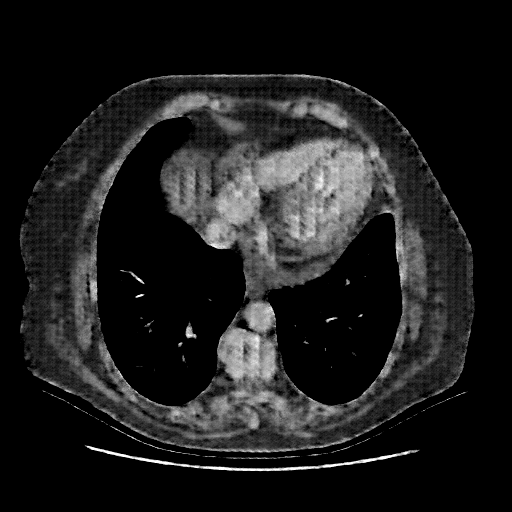

Generated VENOUS CT scan (A→B translation)

No window - Raw intensity values

Lung window (WL -600, WW 1500 β†’ Low βˆ’1350, High +150)

Mediastinum window (WL 40, WW 400 β†’ Low βˆ’160, High +240)